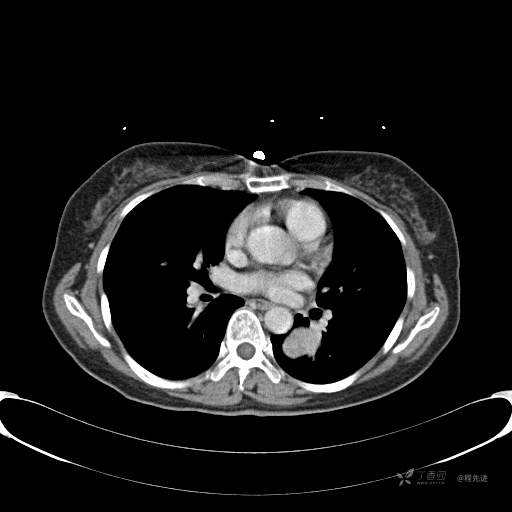

患者性别:女

患者年龄:57岁

简要病史:体检发现

CT增强

平扫CT值约40HU(未上传图像),增强后动脉期CT值约70HU,静脉期CT值约97HU。

肺硬化性血管瘤 (20)